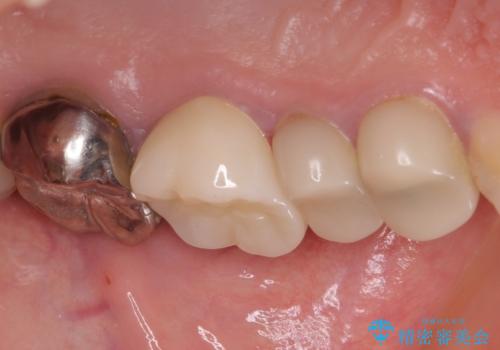

- 笑ったときに見てしまう上顎奥歯の銀歯を気にして来院された患者様です。

折角セラミッククラウンを装着するので、根管治療を行った後に補綴治療を行うこととしました。

他にも目立つ銀歯がありましたが、最も気にしている2本を優先して行うこととしました。

結婚式前にはクリーニングやホワイトニングを行い、その後他の歯を治療していく予定です。